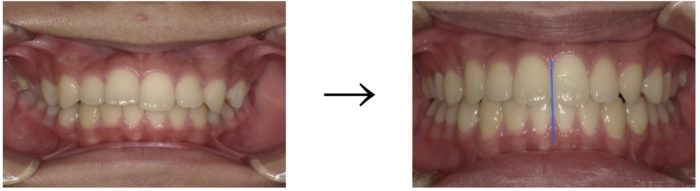

◼︎正面 Before→After

前歯のガタつきがしっかりと改善され、歯列全体がきれいに整いました。

さらに、正中:上の歯と下の歯の中心(写真の青線)を合わせることで、見た目のバランスも美しく仕上がっています。